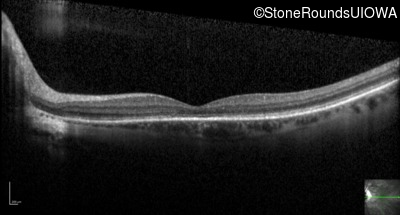

Optical Coherence Tomography - Right - 20/40

Exemplar / OCT Stack

OCT Stack